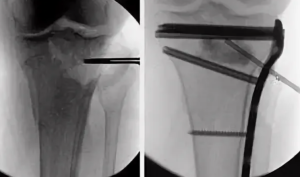

Произвели разметку суставной поверхности прототипа (рис. 3) и определили ключевые фрагменты, — задне-латеральный и передне-латеральный, точки выхода перелома — в передне-центральном и задне-медиальном квадратах. На основании полученных данных выбрали хирургические доступы: заднемедиальный и передне-латеральный. Осуществлён остеосинтез из этих доступов с установкой передне-латеральной пластины и 1/3 трубчатой пластины сзади (рис. 4). Задне-медиальный доступ позволил полностью визуализи ровать перелом заднего края ББК, осуществить репозицию отломков ad occulus и уложить ранее пре моделированную при помощи 3D-прототипа 1/3 трубчатую пластину. Далее пациента перевернули на спину, выполнили передне-латеральный доступ. Метадиафизарный компонент перелома фикси ровали передне-латеральной премоделированной L-образной пластиной, передне-латеральный фраг мент (Chaput) — винтом. Применённый доступ позволил визуализировать передней край вырезки малоберцовой кости для прецизионной репозиции фрагмента Chaput. Послеоперационный период протекал без осложнений, раны зажили первичным натяжением. Больной разрабатывал движения в оперированном голеностопном суставе в течение восьми недель.

По шкале AOFAS AHS сумма баллов составила 82 балла, по шкале VAS-FA — 41 балл, в обоих случаях сумма баллов соответствовала отличным результатам. При оценке рентгенограмм (рис. 5) по критериям mRUST получено 13 баллов, что соответствует перелому в стадии консолидации. Миграции фикса торов, вторичного смещения не выявлено.